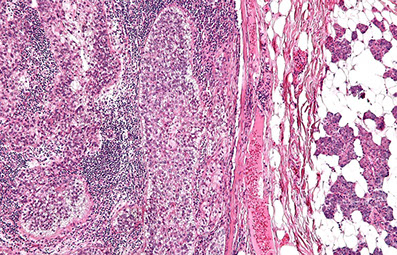

LyP type A

Lymphomatoid papulosis (LyP)

- a CD30-positive lymphophroliferative disorder

Rare, Indolent (self-healing) and chronic papulonodular skin dz c recurrent crops of pruritic papules at different stages of development that arises on the trunk and limbs; ~50 yo M, younger F

- histologically is a CD30+ proliferation of atypical T cells (is part of primary cutaneous CD30+ lymphoproliferatice disorders that includes Primary Cutaenous Anaplastic Large Cell Lymphoma [PC-ALCL] and borderline CD30+ lesions) - has many histologic mimics

- inc freq of prior, coexisting or subsequent lymphoproliferative disorders, usually mycosis fungoides or Hodgkin lymphoma

6 major subtypes:

Type A (MC, ~3/4): Hodgkin-like large atypical cells with intermixed mixed inflam infiltrates (neuts, lymphs, eos, histiocytes)

Type B: MF-like cerebriform cells c predominant epodermotrophic infiltrate

Type C: ALCL-like c large atypical cells and few other inflam cells (distinction from ALCL primarily clinical)

Type D: CD8+ cytotoxic T cell lymphoma-like c pagetoid infiltrate of epidermotrophic small to med-sized atypical CD8+ and CD30+ cells

Type E: Angiocentric infiltrates of small to med pleomorphic cells

Lyp with 6p23.3 rearrangement: Biphasic c small to med cerebriform cells and large atypical cells; usually seen in older adults

Micro: wedge-shaped infiltrate of T cells

IHC: (+) CD30 (CD30+ cells may be aberrant T cells) ,CD3 / 4

- neg ALK, CD8, CD56 (rare +)

DDx: Some immunoblasts, reactive T-cells, can be CD30+, scabies and arthropod bites can have a lot of CD30+ cells too

- Primary cutaneous anaplastic large cell lymphoma (PC-ALCL) can have lots of large ugly cells, the only way you would be able to differentiate is from IRF4 and the clinical history (if waxes and wanes, may consider LyP)

Dx: TCR rearrangement in 2/5 to 5/5 [1]

Px: excellent; although at inc risk secondary or nodal lymphoma such as MF, PC-ALCL and Hodkin lymphoma (up to 1/5)

- not known why there is spontaneous regression, but may be due to simultaneous expression of CD30 and CD95 (Fas) ligand

LyP - Scattered large cells with scattered smaller cells and neutrophils (mixed inflammatory background) wiht eos

LyP

LyP type C with diffuse sheets of CD30+ cells